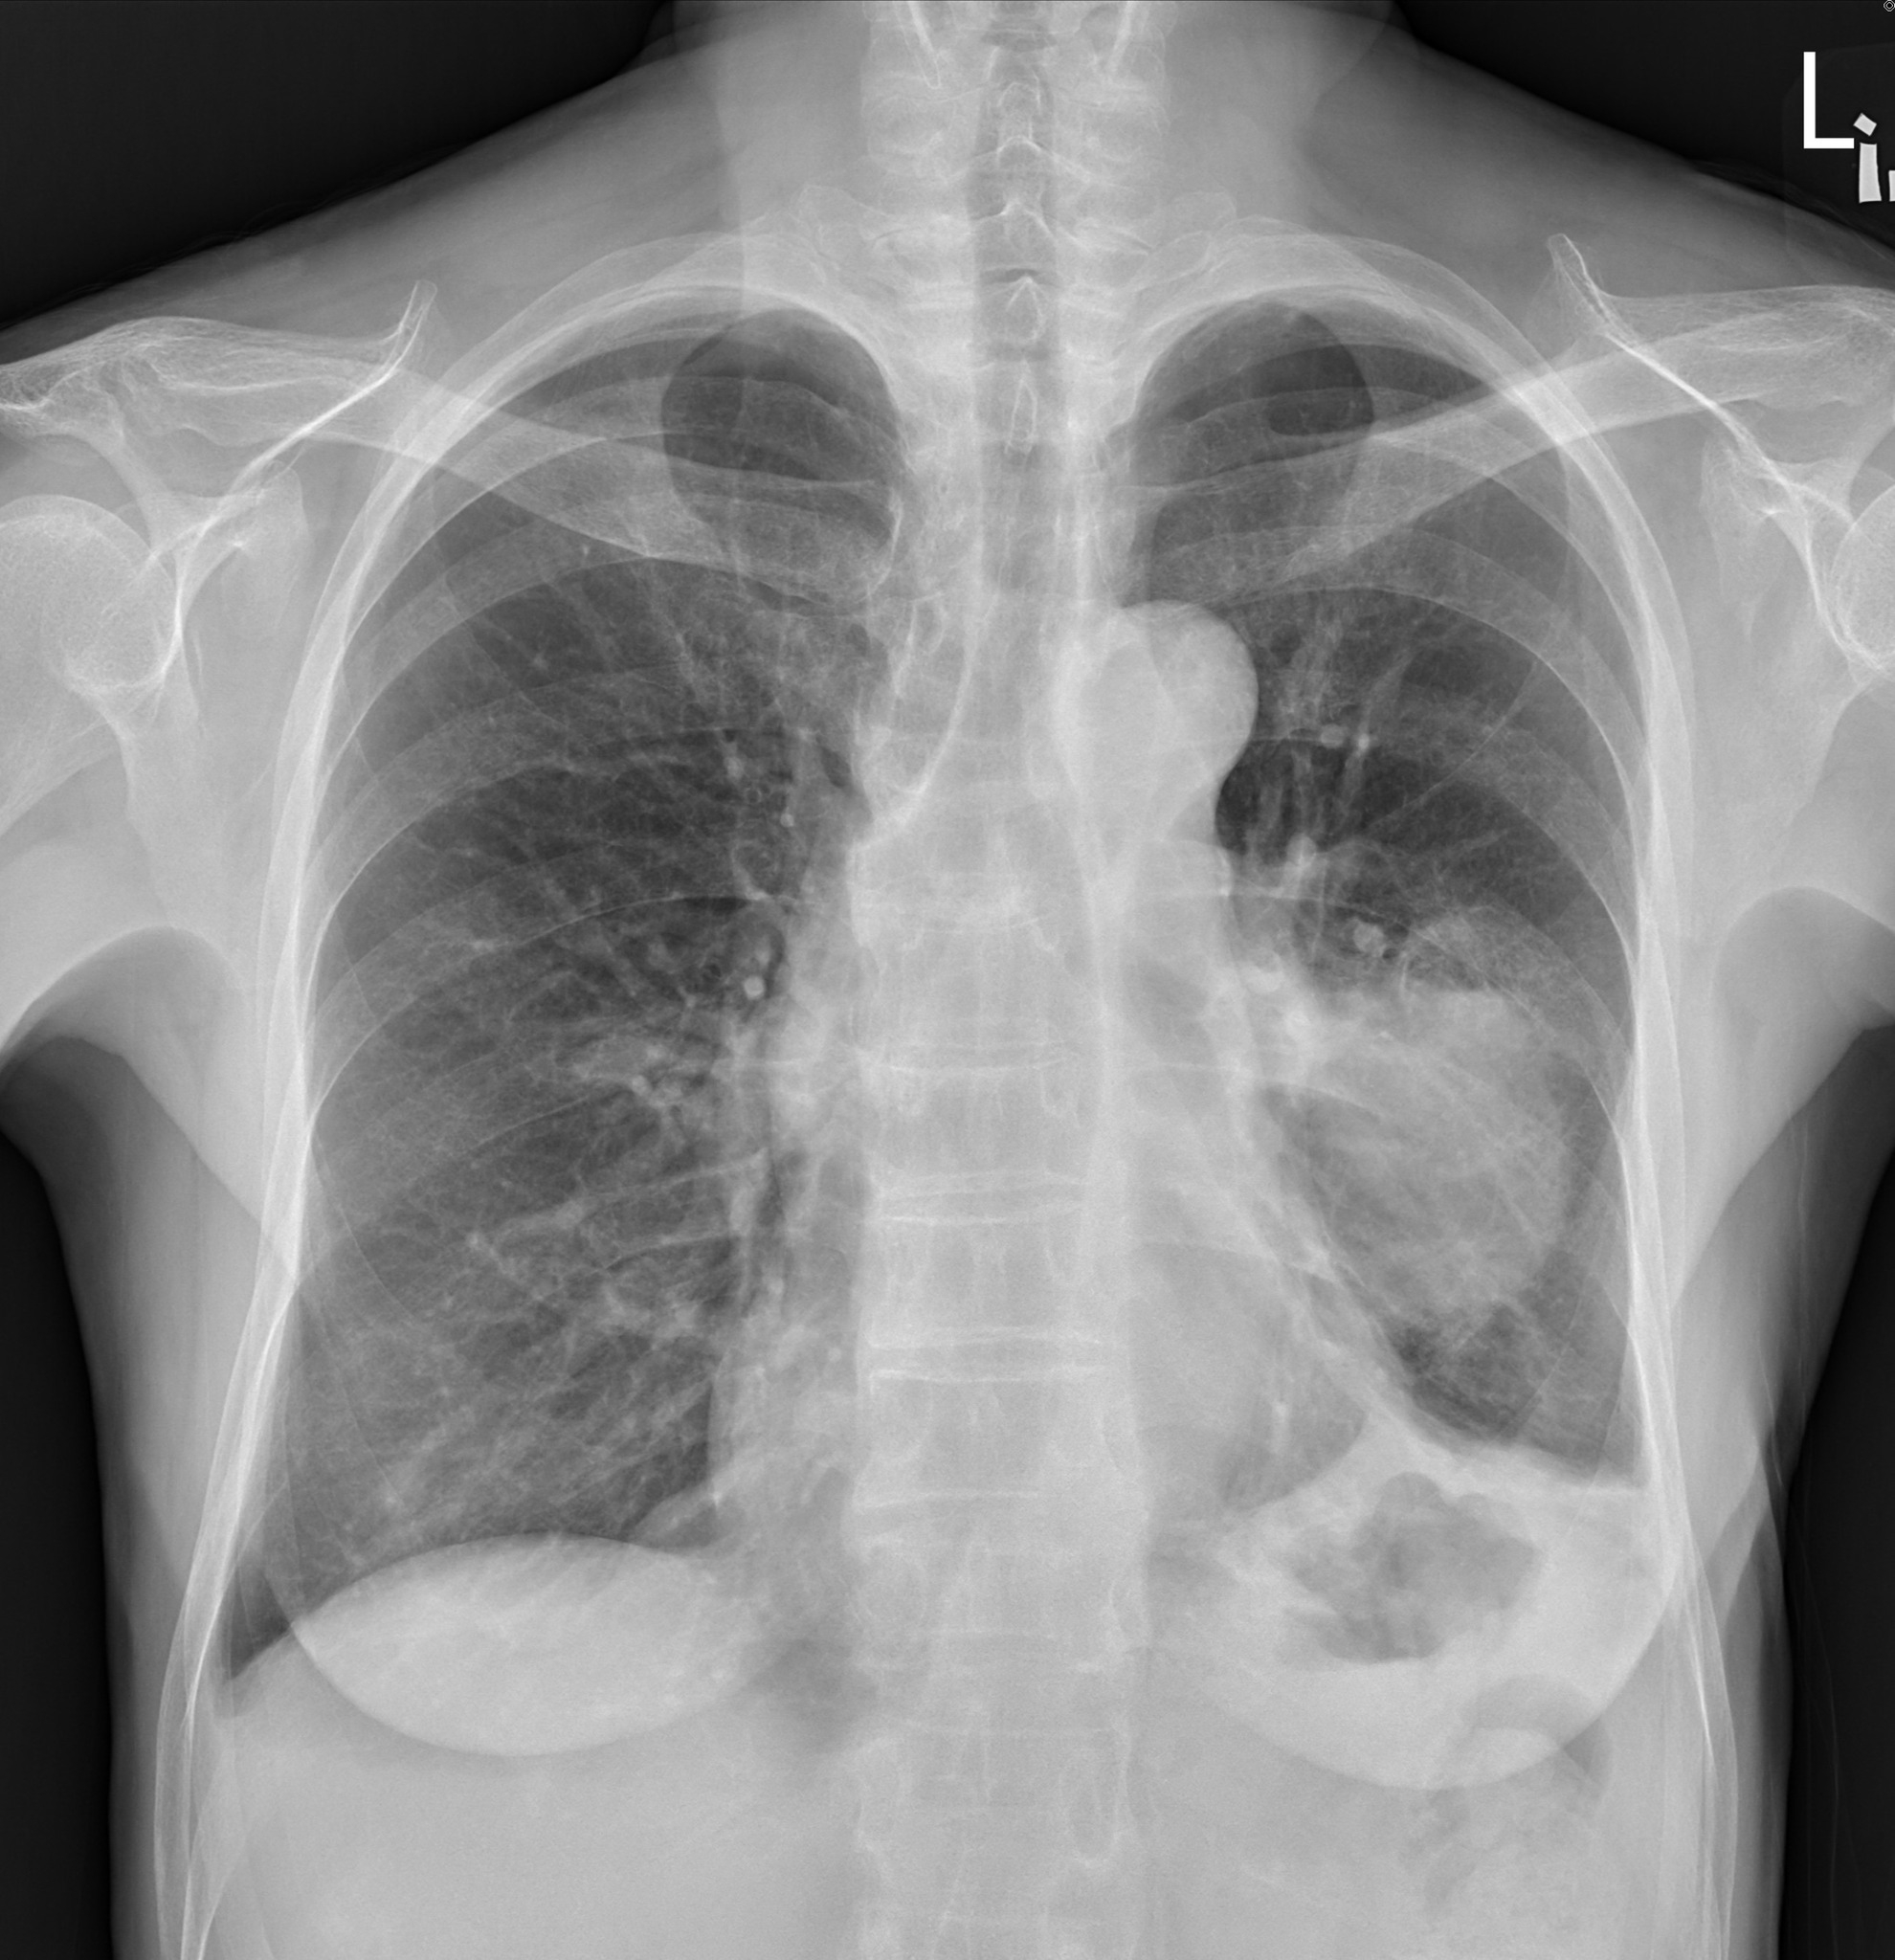

蘇一峰透露,該婦人接受X光檢查後,發現肺腫瘤已長達7、8厘米,已不能開刀做手術。對此,他不禁嘆道:「台灣女性忍耐力很強,肺癌等到有症狀常常都是末期。在台灣定期檢查肺癌真的非常需要,不能等到有症狀才來看醫師(生)......」

May be an image of xray